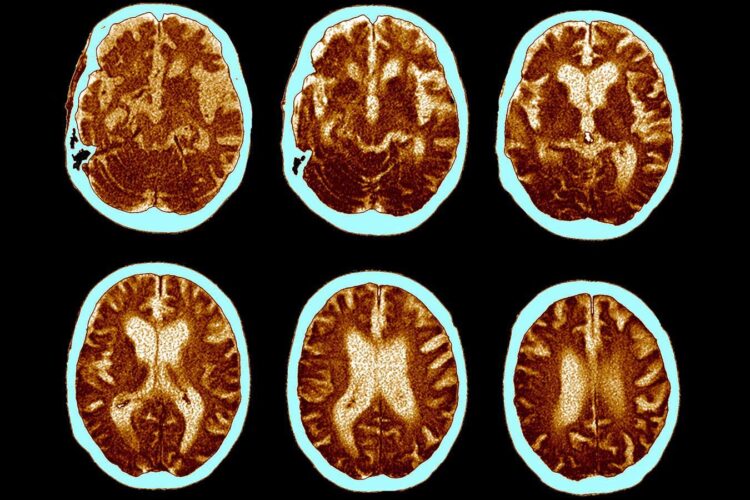

W 2025 roku mają zakończyć się dwa zaawansowane badania kliniczne, które ocenią skuteczność semaglutydu w terapii wczesnych stadiów choroby Alzheimera. Wyniki tych badań mogą stanowić przełom, który pozwoli na lepsze zrozumienie możliwości wykorzystania tej substancji do spowalniania postępu choroby. W badaniach tych skupiono się na ocenie wpływu leku na kurczenie się mózgu, jednego z kluczowych objawów choroby Alzheimera. Obecnie istnieją przesłanki, że semaglutyd może nie tylko spowalniać ten proces, ale również przeciwdziałać destrukcyjnym zmianom w strukturach mózgu.